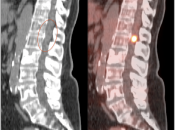

PET/CT is generally not used to decide whether or not a patient has a primary brain tumor (a diagnosis of brain tumor has nearly always already been made by CT or MRI prior to PET/CT scanning). The true value of PET/CT is determining whether or not a known tumor is “high-grade” or not.

- Characterizing lesions as “low-grade” or “high-grade” (with dramatic implications on management & prognosis):

- Low-Grade: Uptake ≈ white matter (may use contralateral centrum semiovale for comparison)

- High-Grade: Uptake > white matter (≈ grey matter)

- As the brain lesion may not clearly identifiable on the non-contrast CT images, it is essential to view the prior MRI (or CT) that lead to the initial diagnosis of “brain tumor”.